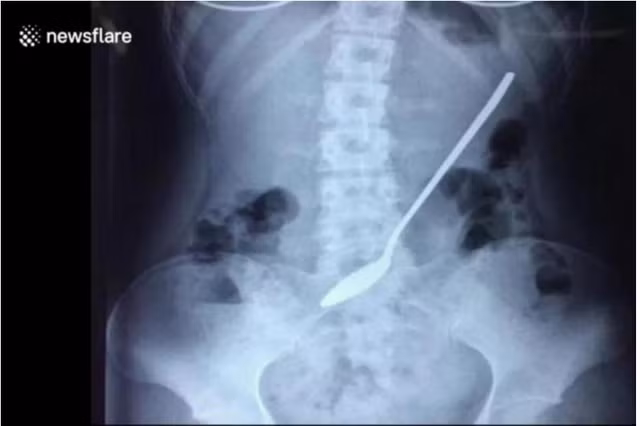

Các bác sĩ tại một bệnh viện Trung Quốc cho biết họ đã loại bỏ thành công dị vật kim loại nằm trong dạ dày của một nữ sinh 18 tuổi. Đó là một chiếc thìa dài 20 cm đã bị cô gái (không biết bằng cách nào) nuốt vào bụng 3 ngày trước.

Đoạn phim quay tại bệnh viện ở Yiwu, tỉnh Chiết Giang, Trung Quốc cho thấy các bác sĩ xem xét hình ảnh chụp X-quang xác định chiếc thìa đang nằm bên trong cơ thể nữ sinh viên trước khi tiến hành phẫu thuật để loại bỏ nó.

Điều đáng chú ý là các bác sĩ cho biết cô gái đã sống chung với chiếc thìa dài 20cm trong bụng suốt 3 ngày liền mới chịu đến bệnh viện. Nguyên nhân là do cô sinh viên chăm chỉ đã cố gắng hoàn thành nốt các bài thi cuối kỳ tại trường học trước khi tìm đến bác sĩ.